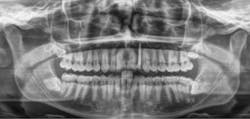

Figure 1a: Pre-op panorex

Figure 5: Post-op panorex